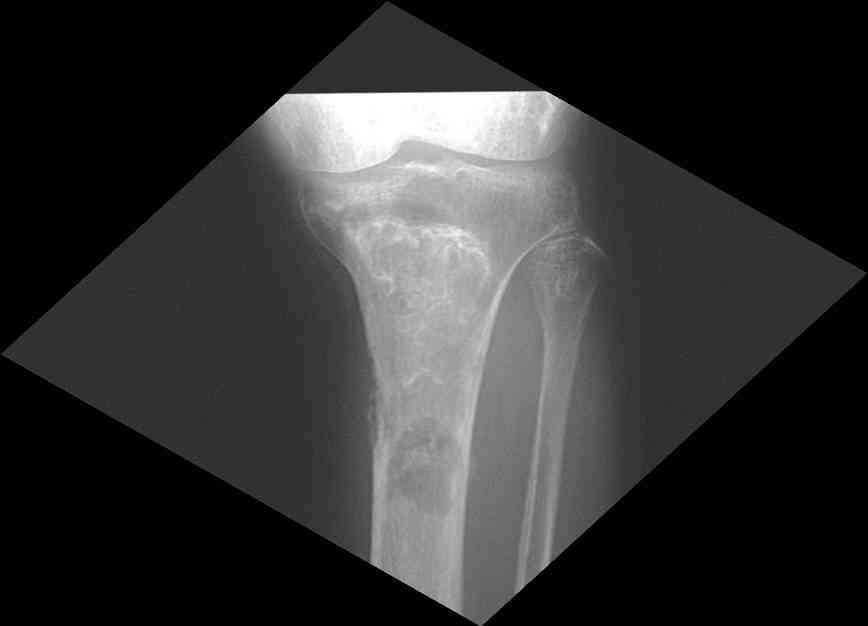

Для примера привожу случай из архива американской ассоциации рентгенологов (ACR) - развитие злокачественной фиброзной гистиоцитомы на левой б.берцовой кости у пациента с множественными инфарктами костного мозга (рис 4,5 - левая, рис 6 - правая)